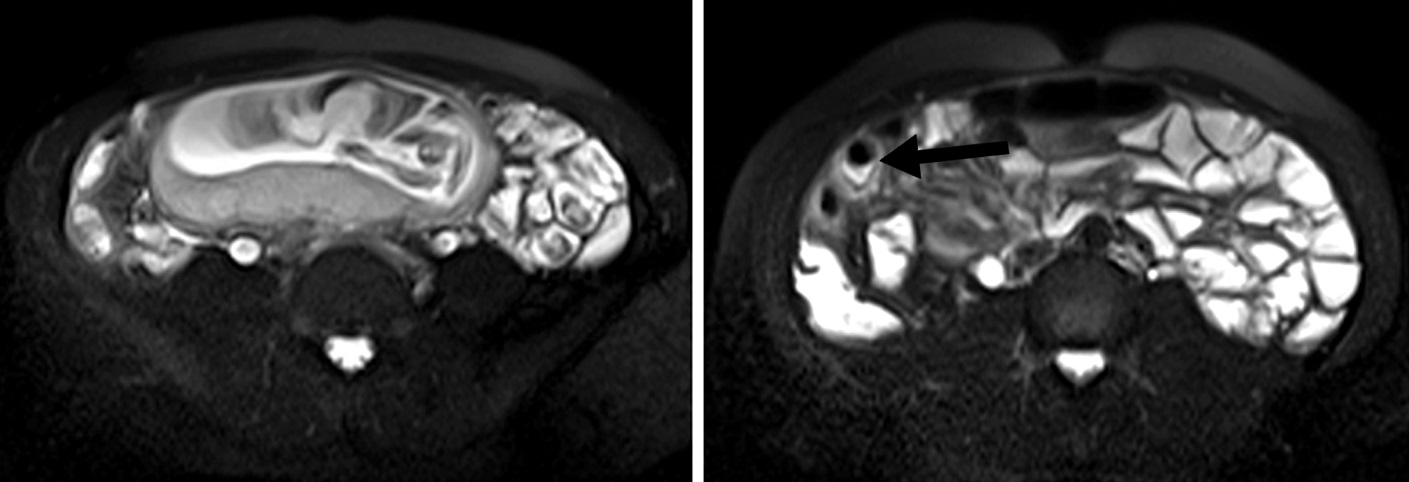

Figura 3

Enfermedad de Crohn a) Secuencia T2 axial sin supresión grasa evidencia engrosamiento parietal de la última asa ileal (flecha blanca).

b y c) secuencias T1 con saturación grasa y gadolinio. Realce estrajpgicado dado por realce de la mucosa (flecha larga) y serosa (flecha corta) separadas por la capa submucosa edematosa (asterisco).